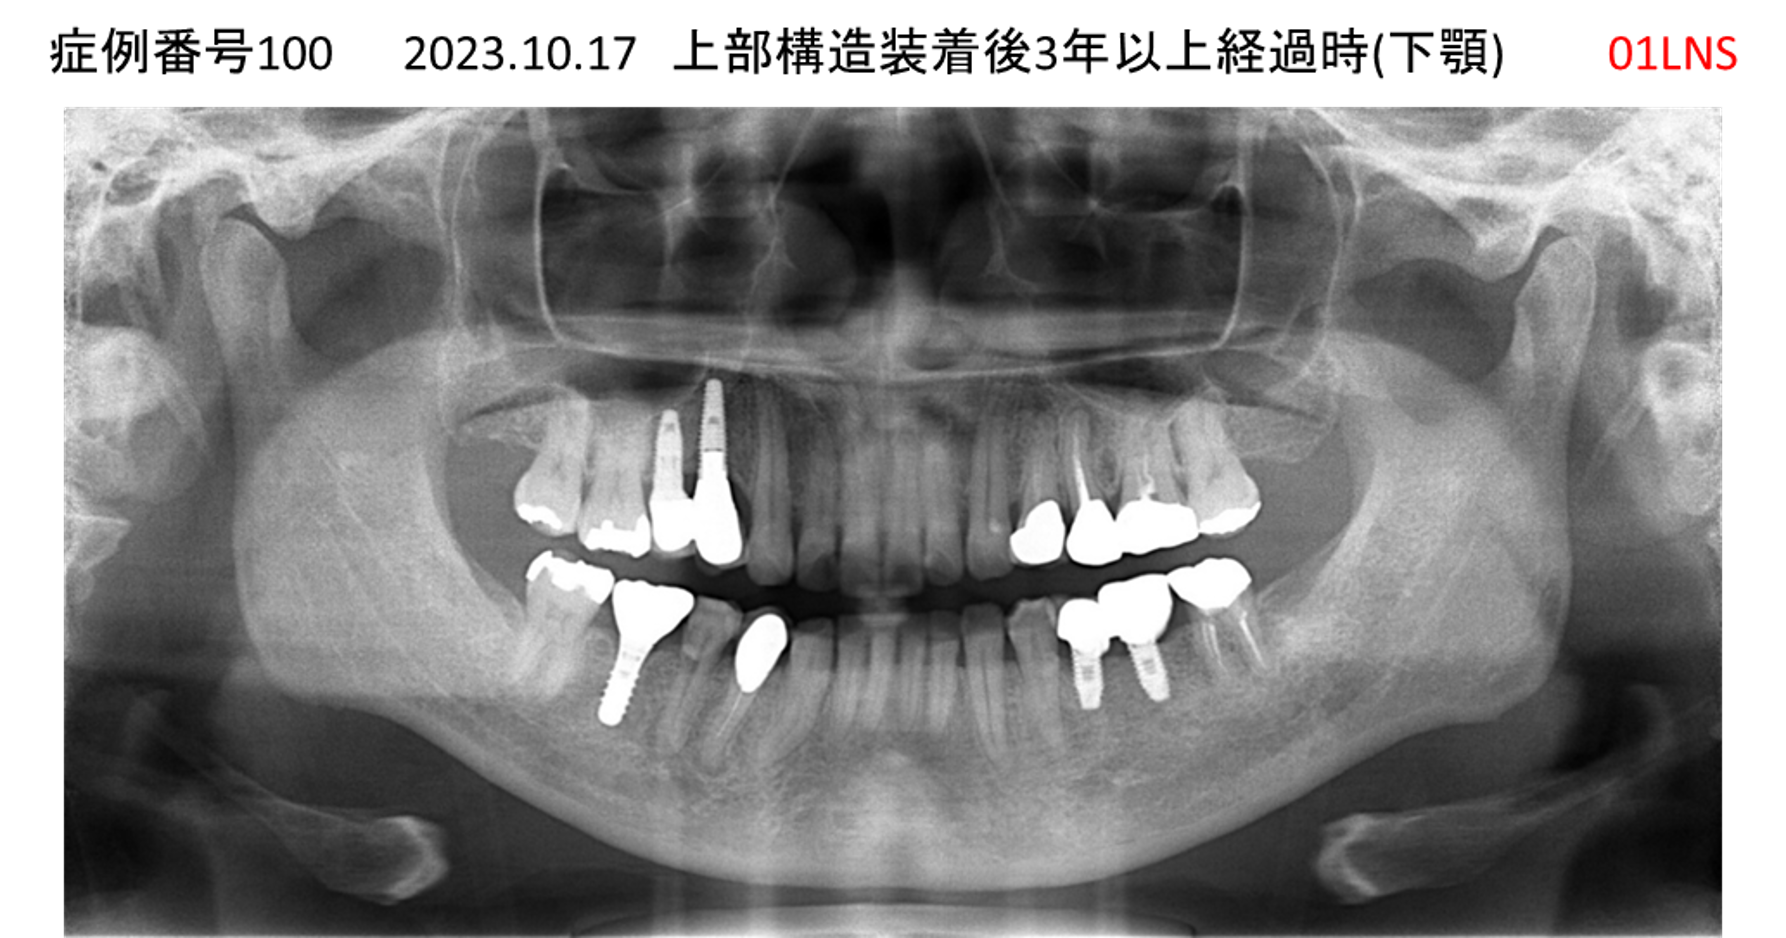

左下の奥歯が痛い患者様のインプラント症例

| 治療名称 |

インプラント |

| 治療費用 |

215万円+税 |

| 治療期間 |

5か月 |

| 患者さんの症状(主訴) |

左下の奥歯が痛い。 |

| 治療内容 |

| 治療結果 |

痛み無く、噛める。 |

| 治療の注意点(リスク/副作用) |

インプラントが壊れたら再治療が必要 |